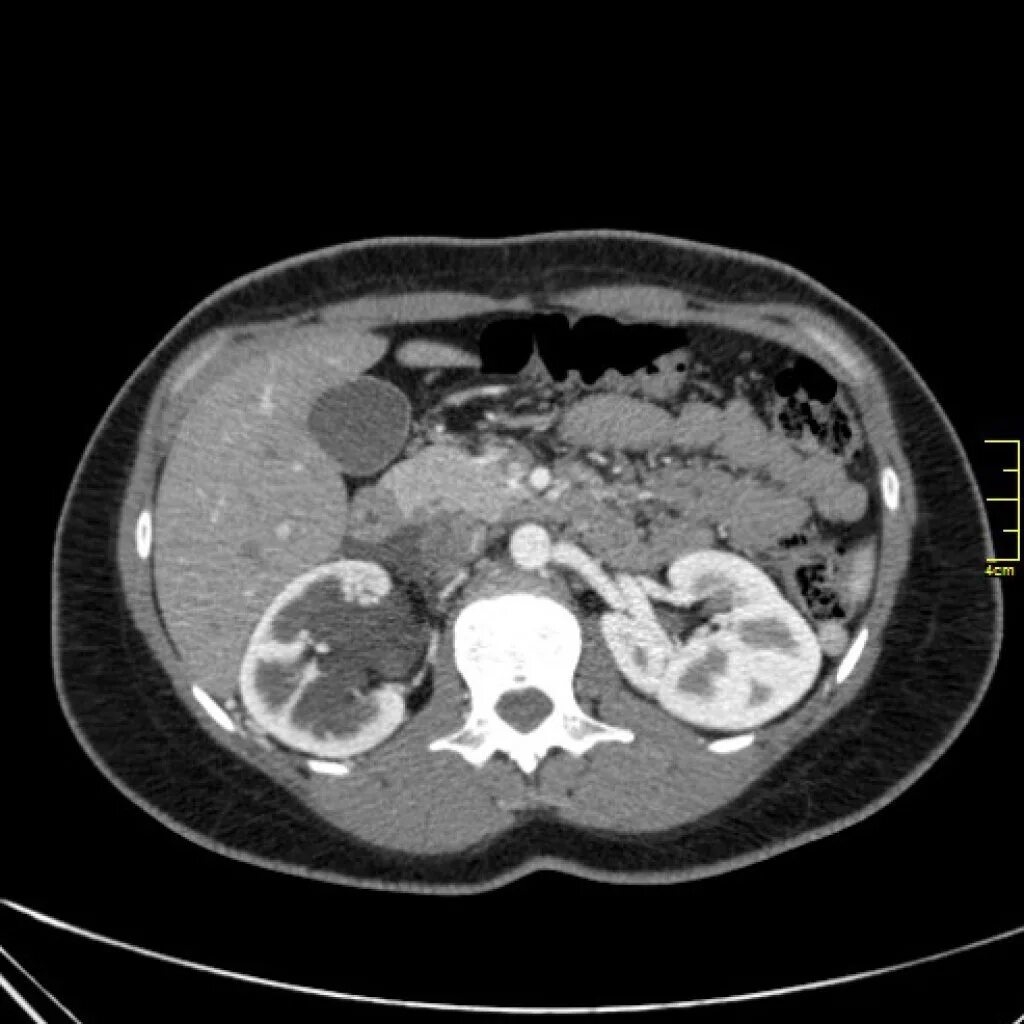

Кортикальная киста почки